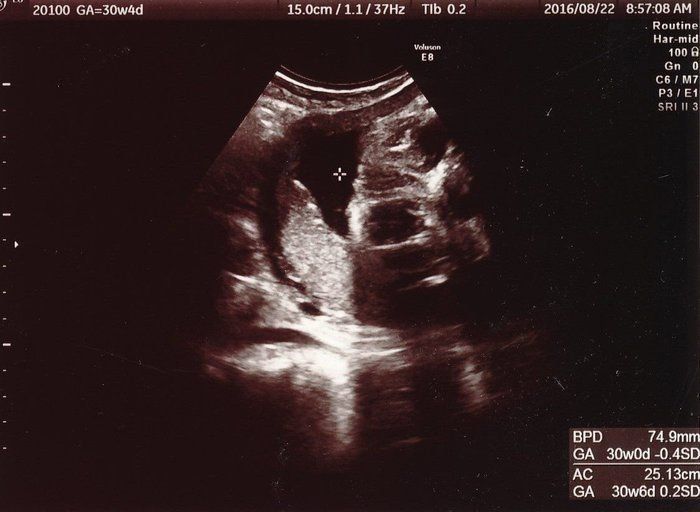

かえるさんの妊娠30週目のエコー写真

赤ちゃんはおなかの中でぐるぐるまわり、毎晩ぼこぼこ蹴られました。お風呂~就寝にかけて元気に動き回るので、なかなか寝付けませんでした。身体を動かしてストレス発散をしようと思い立ち、ピラティスやヨガに通いました。産前にお世話になったスタジオには、今も子連れで通い続けています。臨月・産後をとおして、運動で体重管理やリフレッシュしながらなんとか乗り切りました。